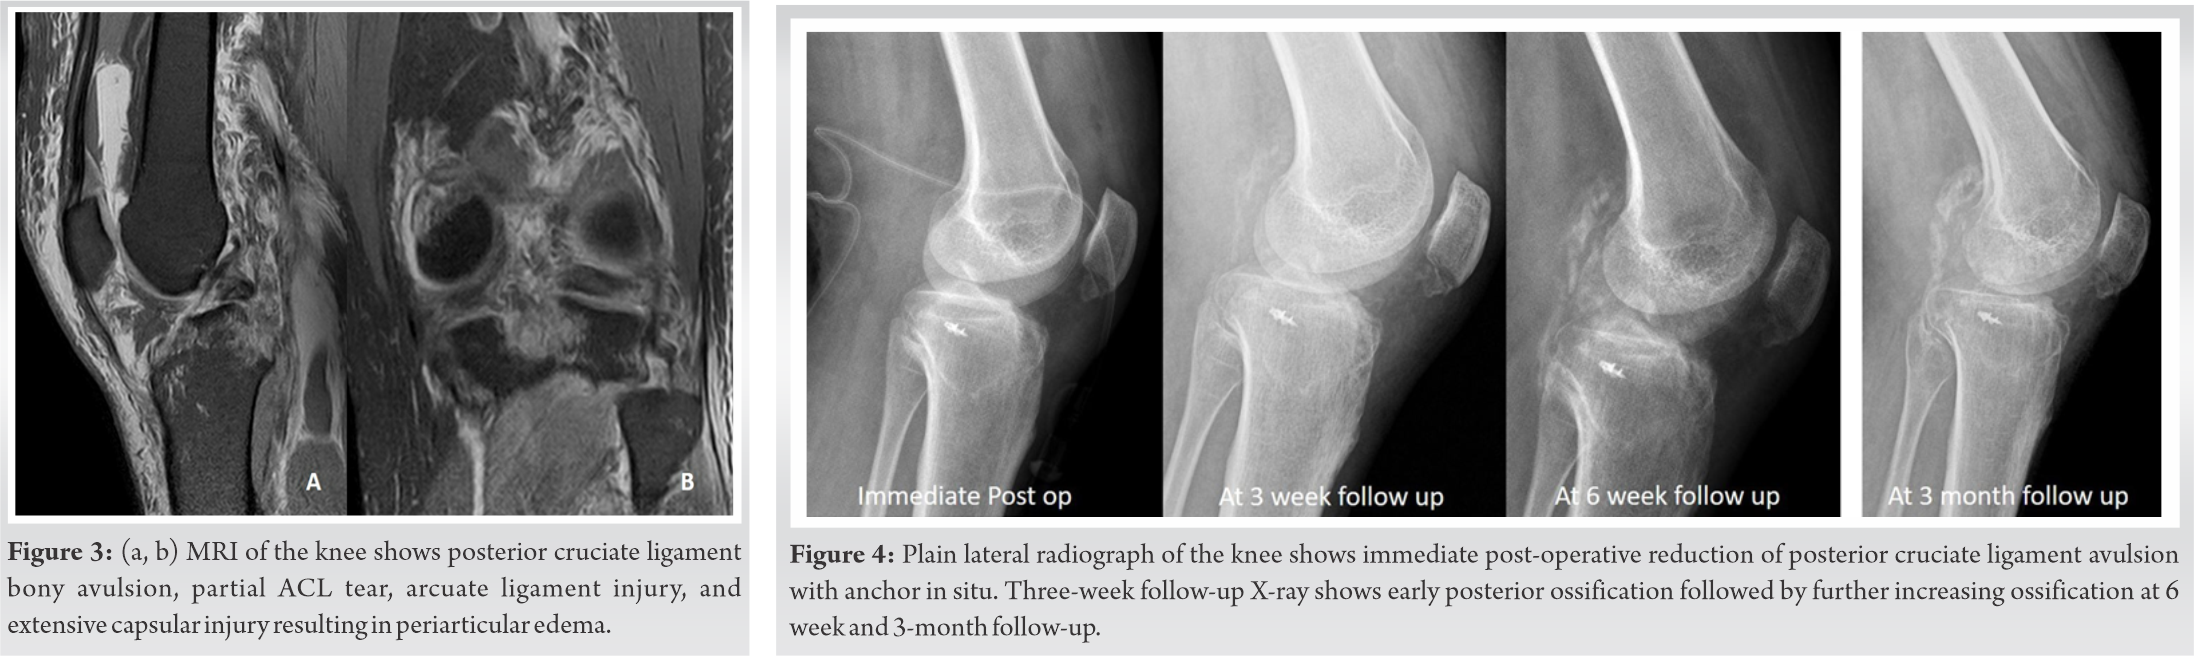

A surgical excisional biopsy of the lesion was planned. After regional anaesthesia, the limb was betadine scrubbed, painted, and draped. Around 10 cm long skin incision was made over the swelling. Superficial peroneal nerve was dissected and the lesion was exposed (Fig. 3). The lesion extended beneath the extensor retinaculum to the dorsum of the foot (Fig. 4). The Extensor retinaculum was cut and the lesion was thoroughly excised. The Extensor retinaculum was repaired and wound closure was done.